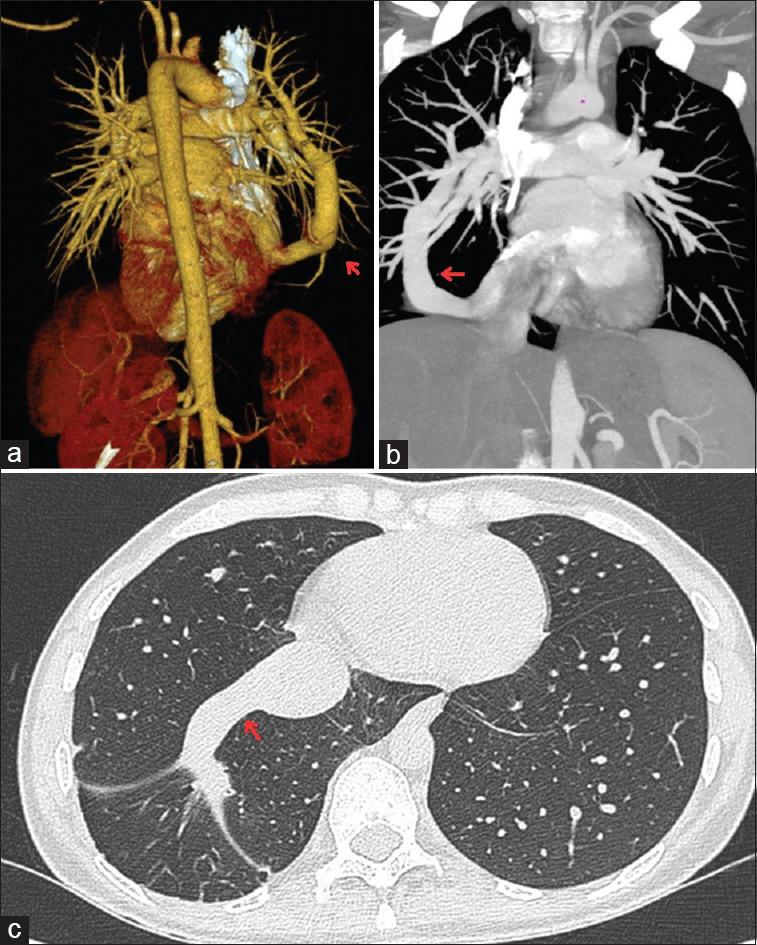

Abstract: Welcome to this radiology challenge. Follow the clues to diagnose a young woman presenting with an unusual and persistent cough. Let us dive into the clinical case and see if you can figure out the cause.